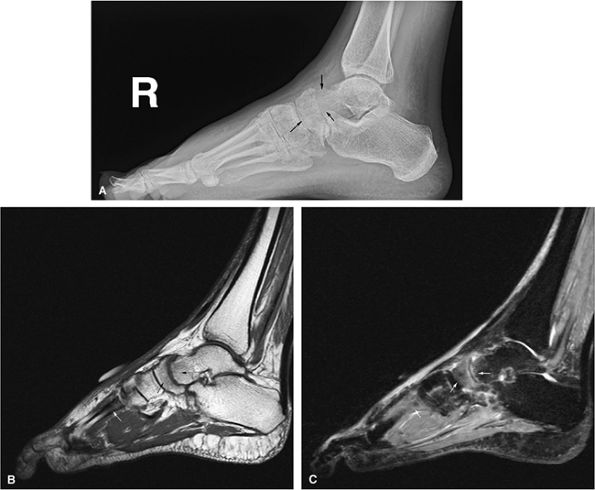

FIGURE 13.95 ● Reflex sympathetic dystrophy (Sudeck atrophy). (A) Lateral radiograph shows demineralization of the talus and navicula (arrows). (B) Sagittal T1-weighted sagittal image shows subtle subarticular low-signal-intensity marrow of the talus and navicula (black arrows). Low-signal-intensity marrow of a metatarsal is also seen (white arrow). (C) Corresponding sagittal STIR image shows marrow edema (arrows) with hyperintense signal intensity.